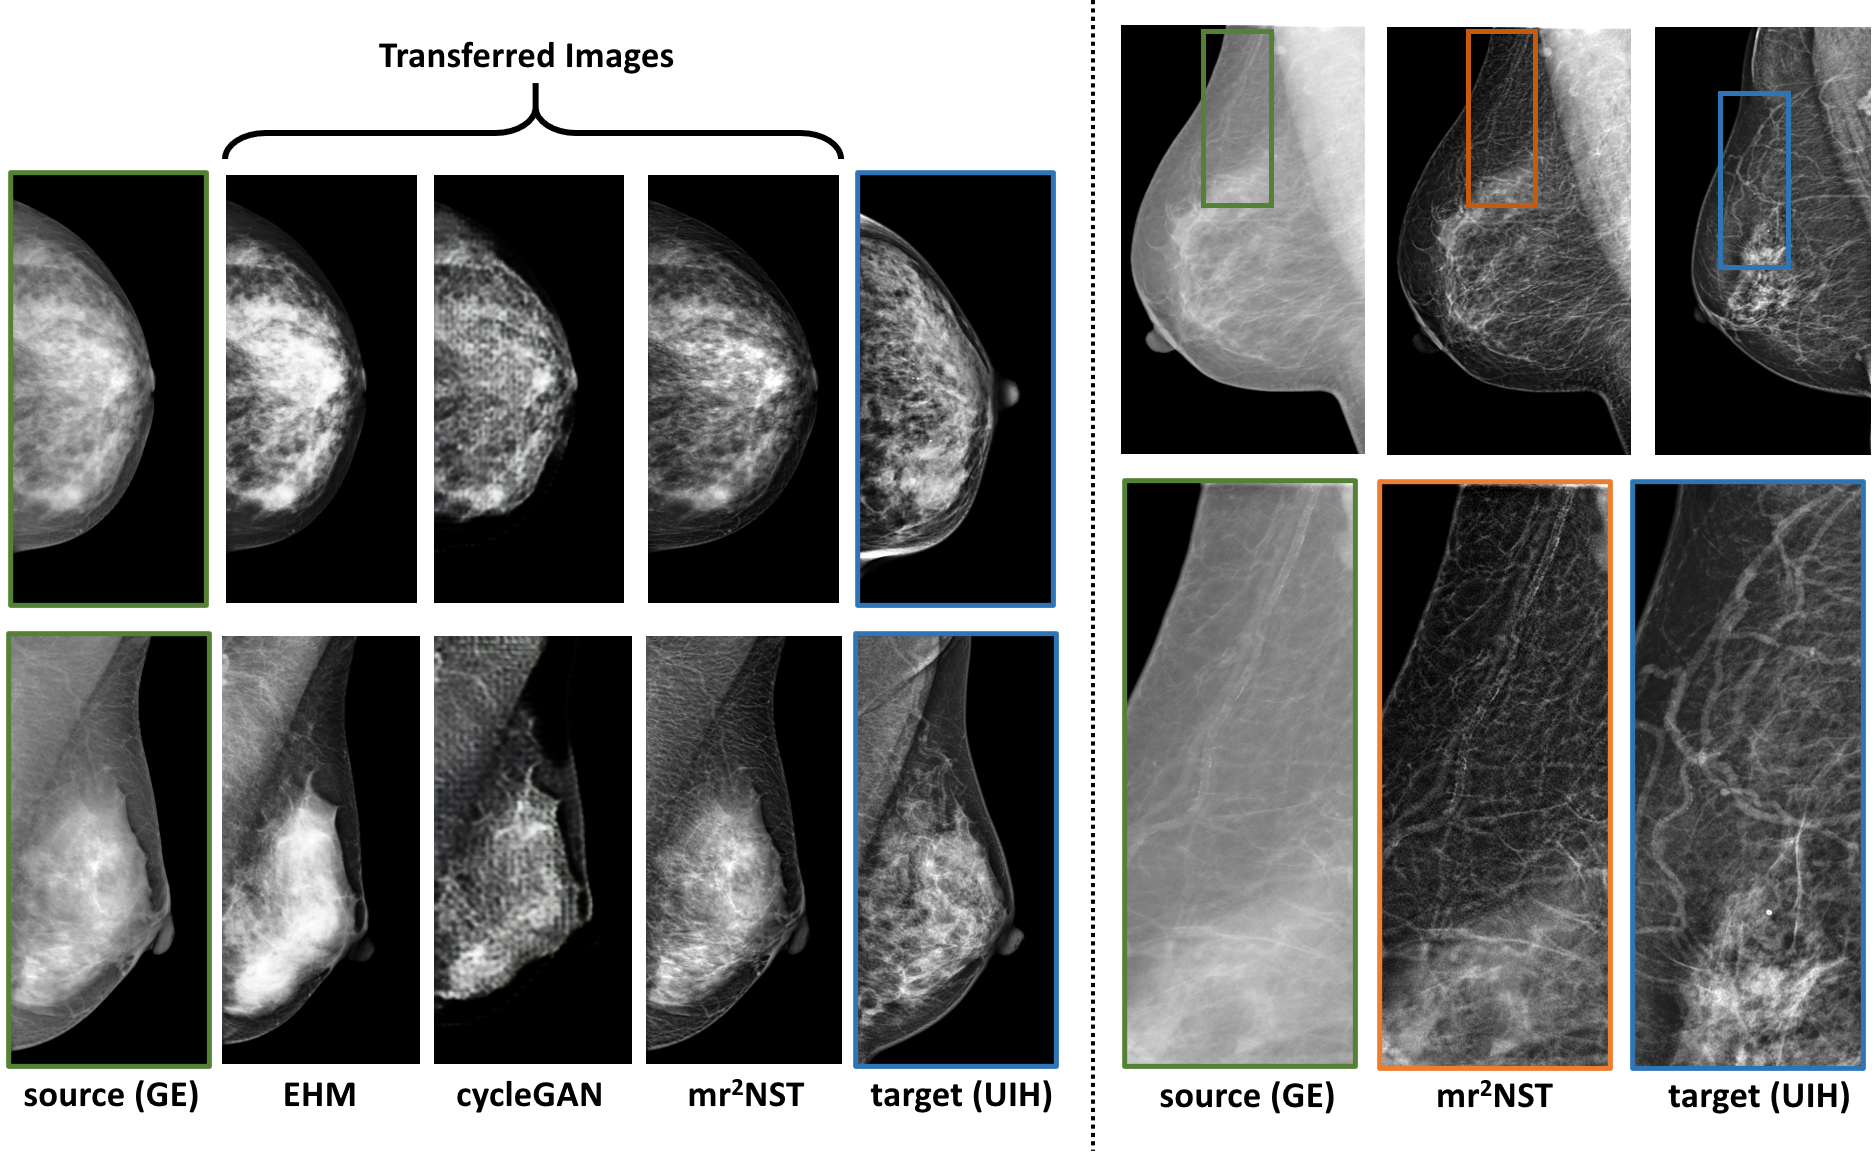

Refer to caption

Figure 4: Visual comparison of mST results from different methods. The right part gives zoom-in comparison in terms of vessel structures.

Fig. 3 illustrates the efficacy of multi-reference and multi-resolution scheme for the mST from GE to UIH. The upper row in Fig. 3 shows better enhance on glandular tissues with 5 reference images on a case with high density, while the lower row suggests the calcification can be better enhanced by fusing the transferred images from all three scales. Fig. 4 shows the mST results from our mr2NST and the baselines of cycleGAN and EHM. From visual comparison, the quality of the transferred images from mr2NST are much better. The cycleGAN requires large GPU memory and can’t support mST in high resolution. Meanwhile, referring to the right part of Fig. 4, mr2NST can preserve the details of vasculature after the mST.